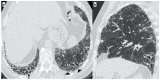

Background: Idiopathic pulmonary fibrosis (IPF) is a progressive fibrosing interstitial lung disease (ILD). This prospective observational study aimed at the evaluation of any correlation between genetic variants associated with IPF susceptibility and high-resolution computed tomography (HRCT) patterns. It also aimed at evidencing any differences in the HRTC pattern between the familial and sporadic form at diagnosis and after two years.

Methods: A total of 65 IPF patients (mean age at diagnosis 65 ± 10) were enrolled after having given written informed consent. HRCT and genetic evaluations were performed.

Results: A total of 19 familial (mean age 62 ± 15) and 46 sporadic (mean age 70 ± 9) IPF patients were enrolled. A statistically significant difference was evidenced in the HRTC pattern at diagnosis between the two groups. Sporadic IPF patients had a predominantly usual interstitial pneumonia (UIP) pattern compared with those patients with familial IPF (60.0% vs. 21.1%, respectively). Moreover, familial IPF patients had more alternative diagnoses than those with sporadic IPF (31.6% vs. 2.2%, respectively). Furthermore, there was a slight increase in the typical UIP pattern in the familial IPF group at two years from diagnosis.